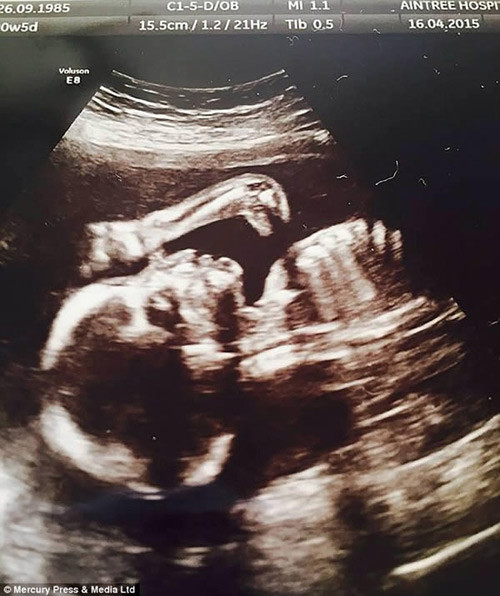

Cặp bố mẹ trẻ Amy Cregg và Leighton Hargreaves từ Accrington, Lancs nước Anh cảm thấy vô cùng tự hào và hạnh phúc khi hình ảnh chụp siêu âm cậu con trai Leo 31 tuần tuổi như nở nụ cười khi còn đang trong bụng mẹ.

Hiện tại, bố mẹ bé cho biết kể từ sau khi sinh đến nay đã 4 tháng tuổi, Leo thường xuyên nở nụ cười với mọi người, ngay cả trong lúc ngủ. Một công ty người mẫu nhí đã liên lạc với cha mẹ của Leo với mong muốn mua lại bức hình siêu âm nụ cười của cậu bé vì cảm thấy khá thú vị.